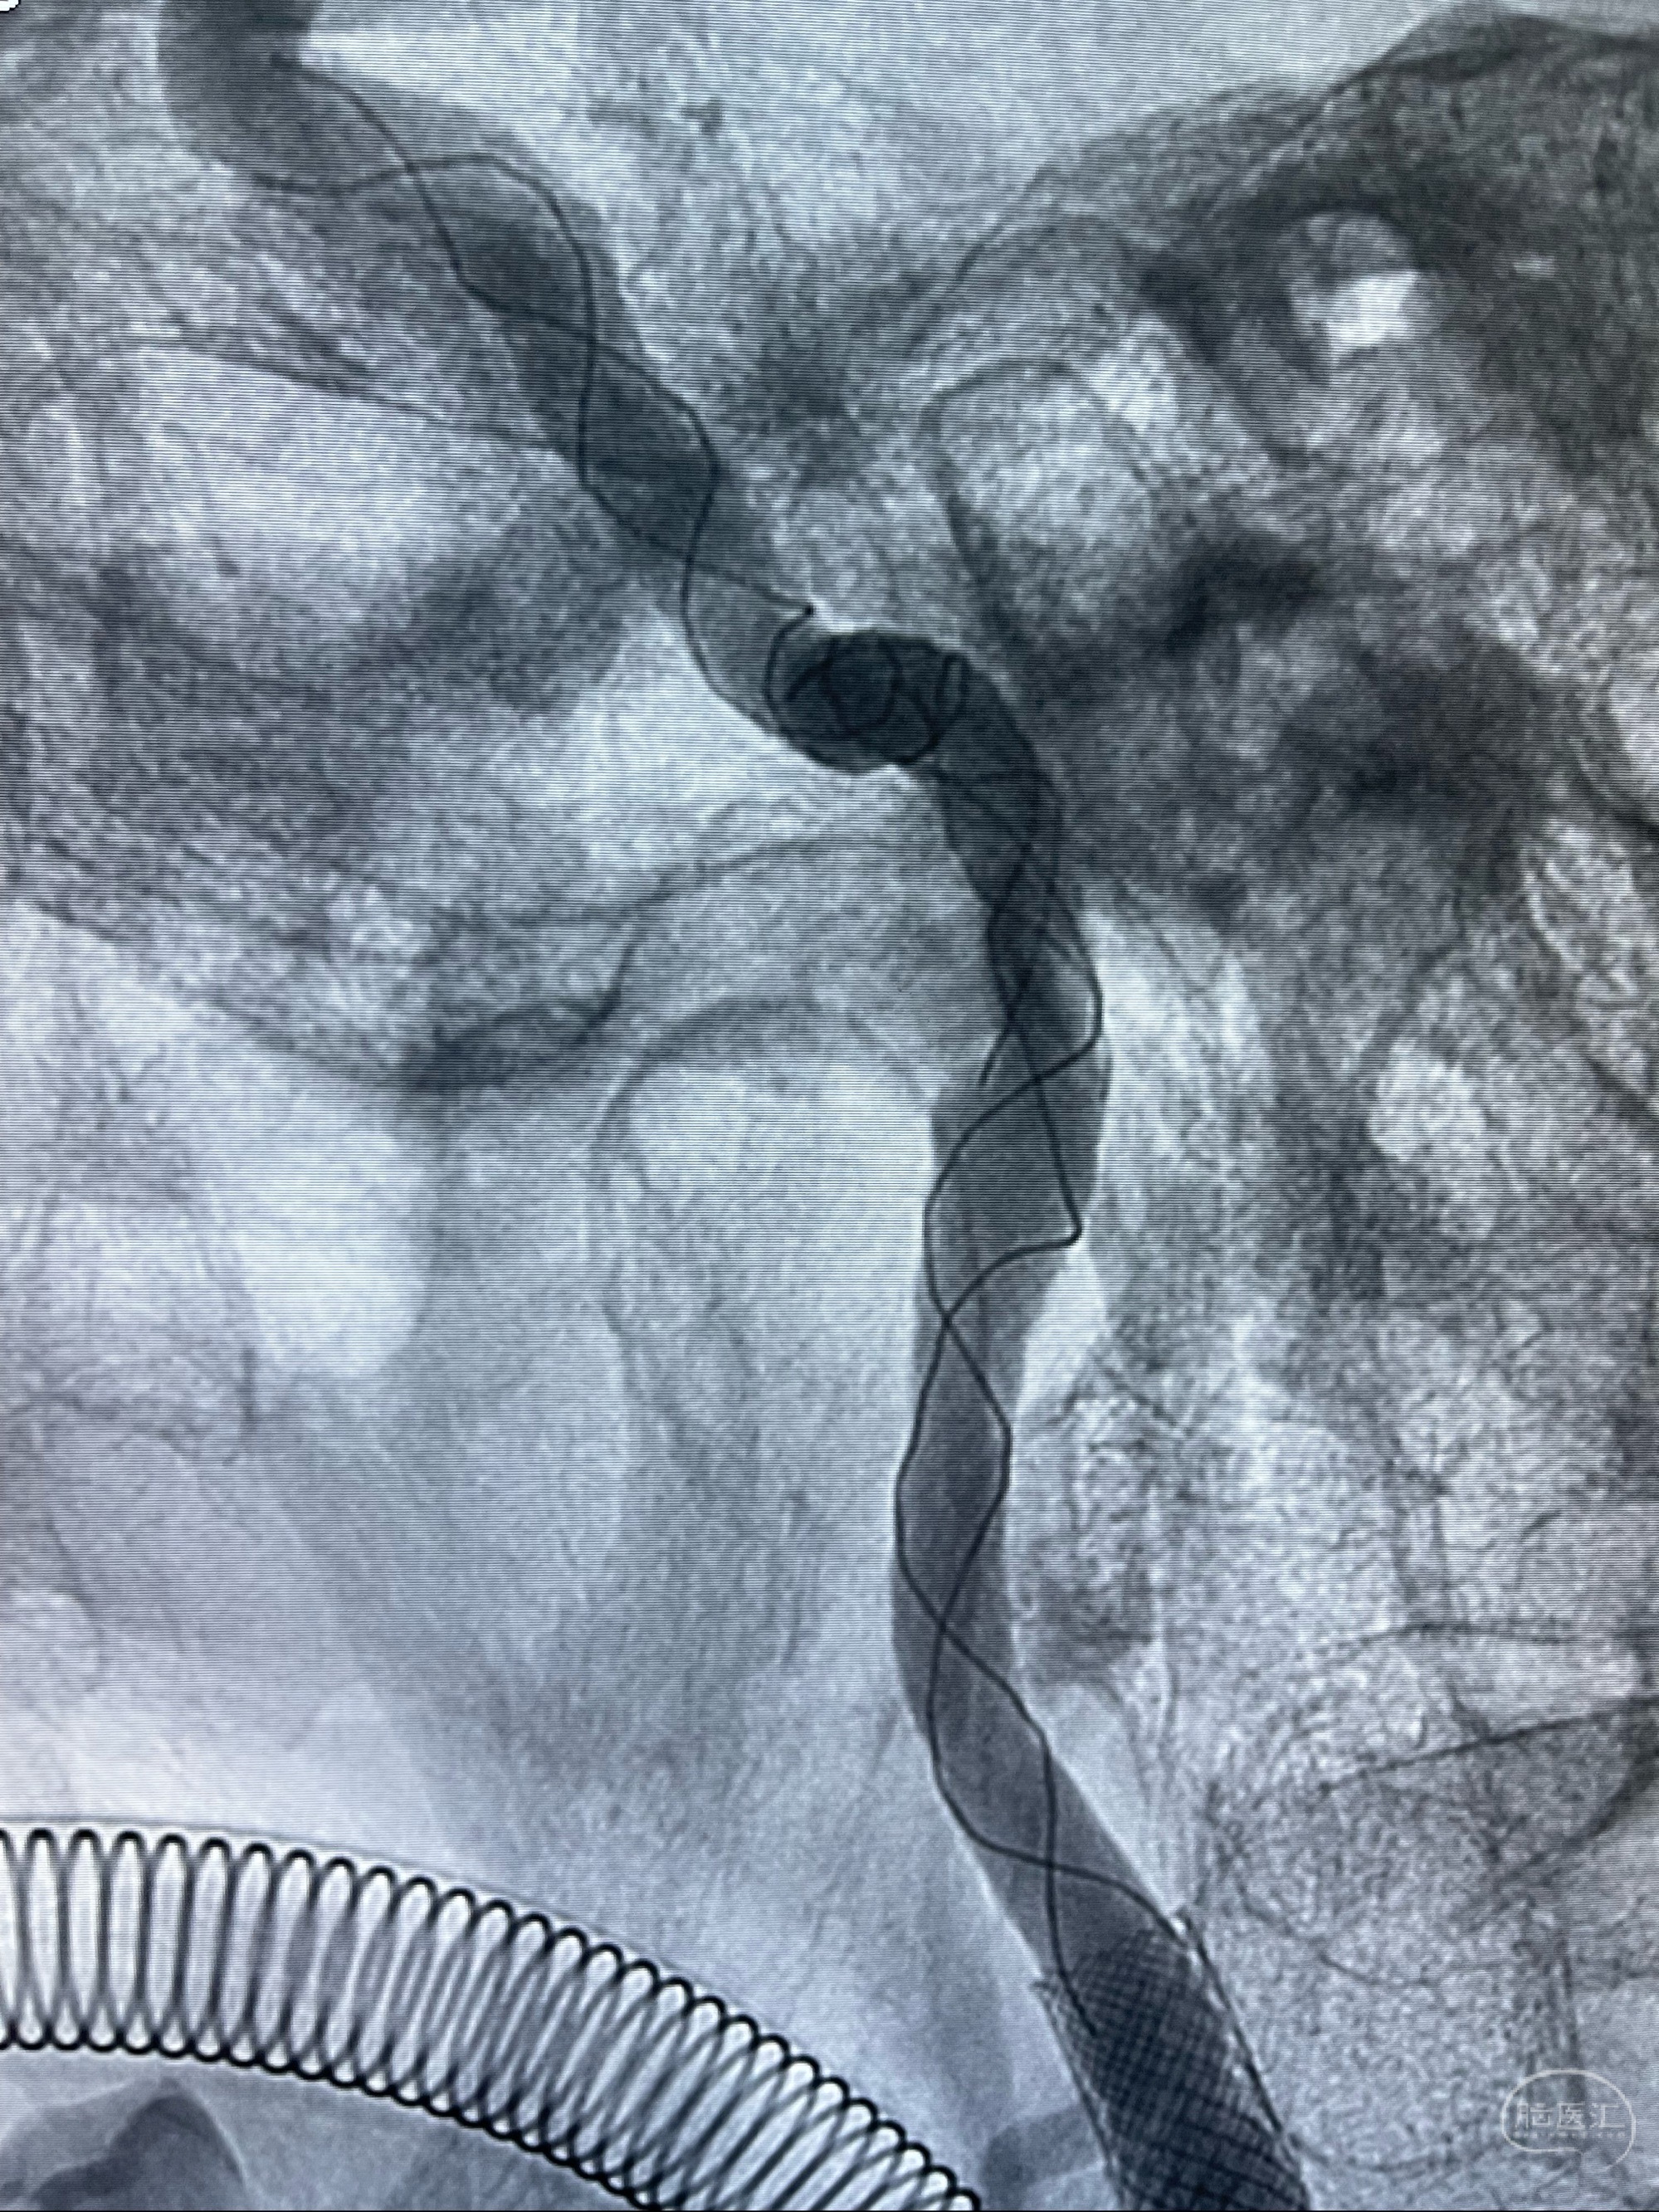

088NeuroMAX100cm长鞘在125cmMPA及黑泥鳅导丝引导下超选择性插入右侧颈内动脉支架内

经导引导管造影显示支架远端颈内动脉不规则狭窄伴局部充盈缺损,同时行全身肝素化5ml

路径图下4-20mm球囊在导丝引导下超选择性至狭窄段,以6-8个大气压扩张,持续30s

泄除球囊造影显示局部管腔扩张佳

后移球囊至颈段狭窄段,以8-12个大气压扩张,持续30s后泄除球囊

即刻造影显示狭窄扩张佳